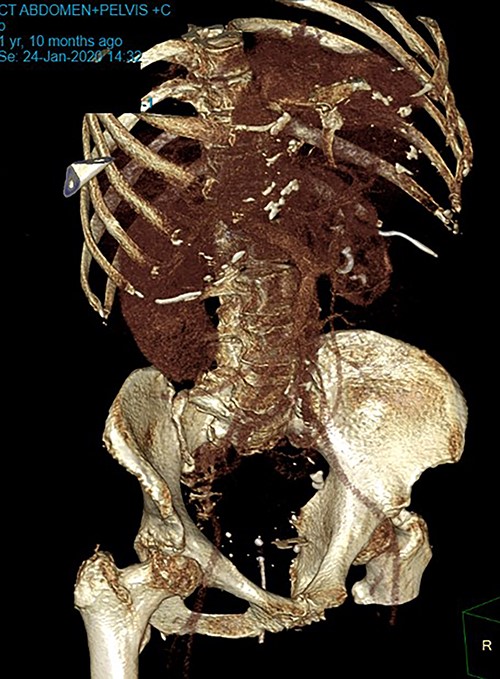

Patient SC is a 72-year-old lady who presented with urosepsis secondary to a left-sided distal ureteric renal stone. Her medical history includes ischemic heart disease, chronic pulmonary obstructive airway disease, type 2 diabetes mellitus, Parkinson’s disease and a previous open cholecystectomy. She was admitted to the intensive care unit and a left-sided nephrostomy tube was inserted. Initial CT imaging incidentally identified a ‘bread clip’-shaped FB in the distal jejeunum (Figs 1 and 2). There was no evidence of obstruction nor perforation. Abdominal X-rays failed to show the presence of a FB.

Intraoperatively, an inflamed segment of 5 cm of the mid jejunum was identified, the FB was palpable and appeared to be partially eroding through the serosa. A SB resection was performed with primary stapled anastomosis. The FB was identified as a BC.

Secondly, as shown in the three cases, unless the BC is calcified, abdominal plain films are not a reliable method of tracking nor diagnosing BC ingestion [9–13]. CT is more sensitive, with a sensitivity rate of 67%, but is not consistently reliable on its own [6, 7]. Reconstructed 3D imaging is effective in identifying BCs. Most BCs are made of low-density polystyrene, a type of versatile solid plastic, which are not readily identified on plain film imaging [14, 15]. This non-degradable plastic means that it is usually only a matter of time before a patient develops a complication.